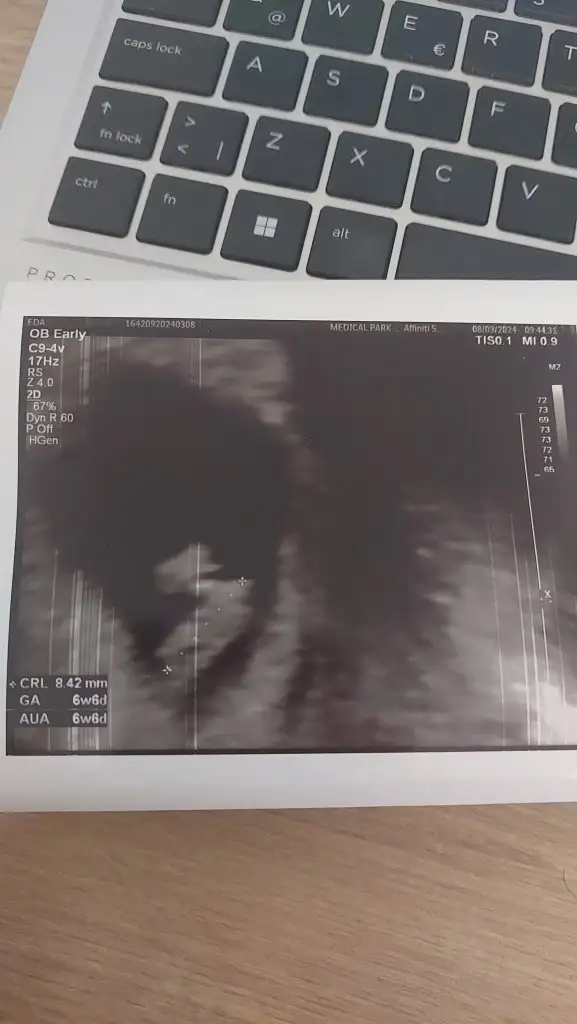

Hayır kalp atışını duymadım daha erken olduğu için bu hafta bitiminde çağırdı doktor aynı kesenin içinde iki tane gördüğü için söyledi diğeri gelişmedi derken anlayamadım gelişmeyen bir durum yok öyle bir sey demedi doktor. Size gelişmediğini mi söyledi doktor ?

hayır ben gittiğimde 7+0 dı. yanı dıgerı neden kalp atısı alınmadı dıye kendım yorumladım.

ultrason kagıdınız var mı merak ettım.

Aaa haklısın 7 haftalıkta gitmişsin dediğin gibi iki kalp atışı olurdu. Peki bebek değilse diğeri için başka bir terim kullanıp o da olabilir gibi birsey dedi mi? Bana iki tane gibi ama farklı açıdan bakınca da değil haftaya net belli olur dedi. Az bir kanama kanalı var dedi fitil verdi onun için de

Bu yolk mu bilmem ama bebişim bu 😁🥰🥰

Kalp atışı duymadım ama kalbinin attığını gösterdi zarar vermemek için açmıyorum sesi dedi ama gördük attığını 💗